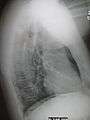

| A chest X-ray showing a very prominent wedge-shape bacterial pneumonia in the right lung. | |